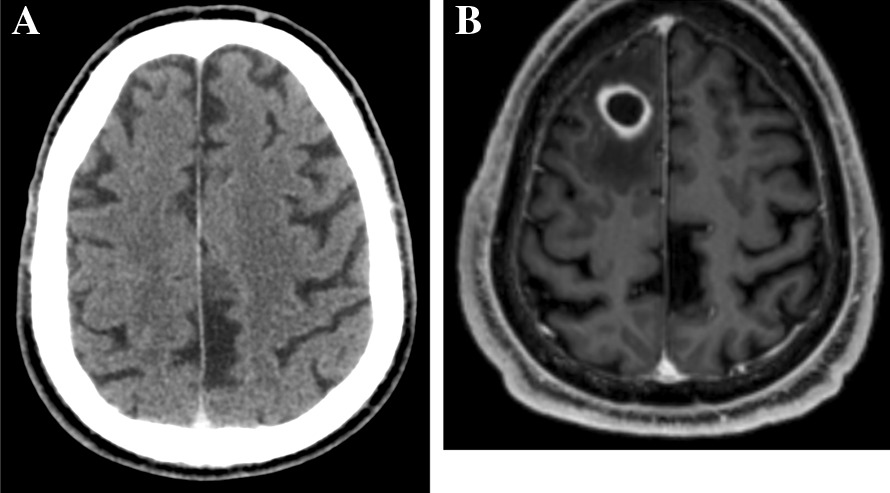

A 65-year-old-man was admitted in the emergency department for seizures. His medical history included diabetes mellitus, arterial hypertension, and smoking. Four months before admission, a chest X-Ray performed because of a persistent cough revealed a lung mass. The lung biopsy yielded a squamous non-small-cell lung cancer with 80% expression of PD-L1. Extended evaluation including a brain CT (Fig. 1A), thoracic CT, abdominal MRI and whole-body PET-scan showed a unique hepatic metastasis. Following consultation with the institutional multidisciplinary team in charge of lung cancer, the patient was treated with intravenous pembrolizumab (anti-PD-1 antibody), started 3 months before admission, as a single-drug regimen, 200 mg every three weeks, with no tolerability or adherence issues.

Fig. 1.

Brain CT before pembrolizumab start, and brain MRI at the time of cerebral nocardiosis diagnosis. A Brain CT before pembrolizumab start (no abnormality). B T1-weighted gadolinium-enhanced brain MRI at the time of cerebral nocardiosis diagnosis: 18 mm right frontal lobe round-shaped lesion with perilesional edema and wall enhancement

On admission, the patient was afebrile, and clinical examination was normal. Routine biochemical and hematology tests were normal, with blood leukocytes count of 7.8 G/l, and serum C reactive protein at 1.1 mg/l. The electroencephalogram performed 12 h after seizures was normal. Brain CT scan found a focal hypodense lesion in the right frontal lobe, further characterized by brain MRI as an intracranial round-shaped lesion with a maximal diameter of 18 mm, low signal intensity on T1-weighted and intermediate signal intensity on T2-weighted images, associated with perilesional edema and wall enhancement on T1-weighted gadolinium-enhanced images (Fig. 1B), suggestive of brain abscess, while brain metastasis could not be ruled out. The patient was transferred to the neurosurgical department for a total removal of the lesion (excision with craniotomy), both for diagnostic and therapeutic purposes. Per-operative macroscopic findings were also suggestive of brain abscess, and empirical antimicrobial therapy was started after surgery with a combination of intravenous ceftriaxone and metronidazole. Microscopic examination revealed numerous filamentous-branching Gram-positive rods. Cultures yielded Nocardia farcinica, identified by MALDI-TOF mass spectrometry. Antibiotic treatment was modified to meropenem 1 g every 8 h associated with cotrimoxazole 1600 mg/400 mg every 8 h and folinic acid. Body-CT did not show any other localization of nocardiosis, while the mass tumor had decreased by 80% after the sixth cycle of pembrolizumab. Drug susceptibility testing found a meropenem MIC of 32 mg/L, while linezolid MIC was 4 mg/L, and cotrimoxazole MIC was 0.5 mg/L. Meropenem was replaced by linezolid 600 mg every 12 h, in combination with cotrimoxazole. Following the diagnosis, additional risk factors for cerebral nocardiosis were ruled out.